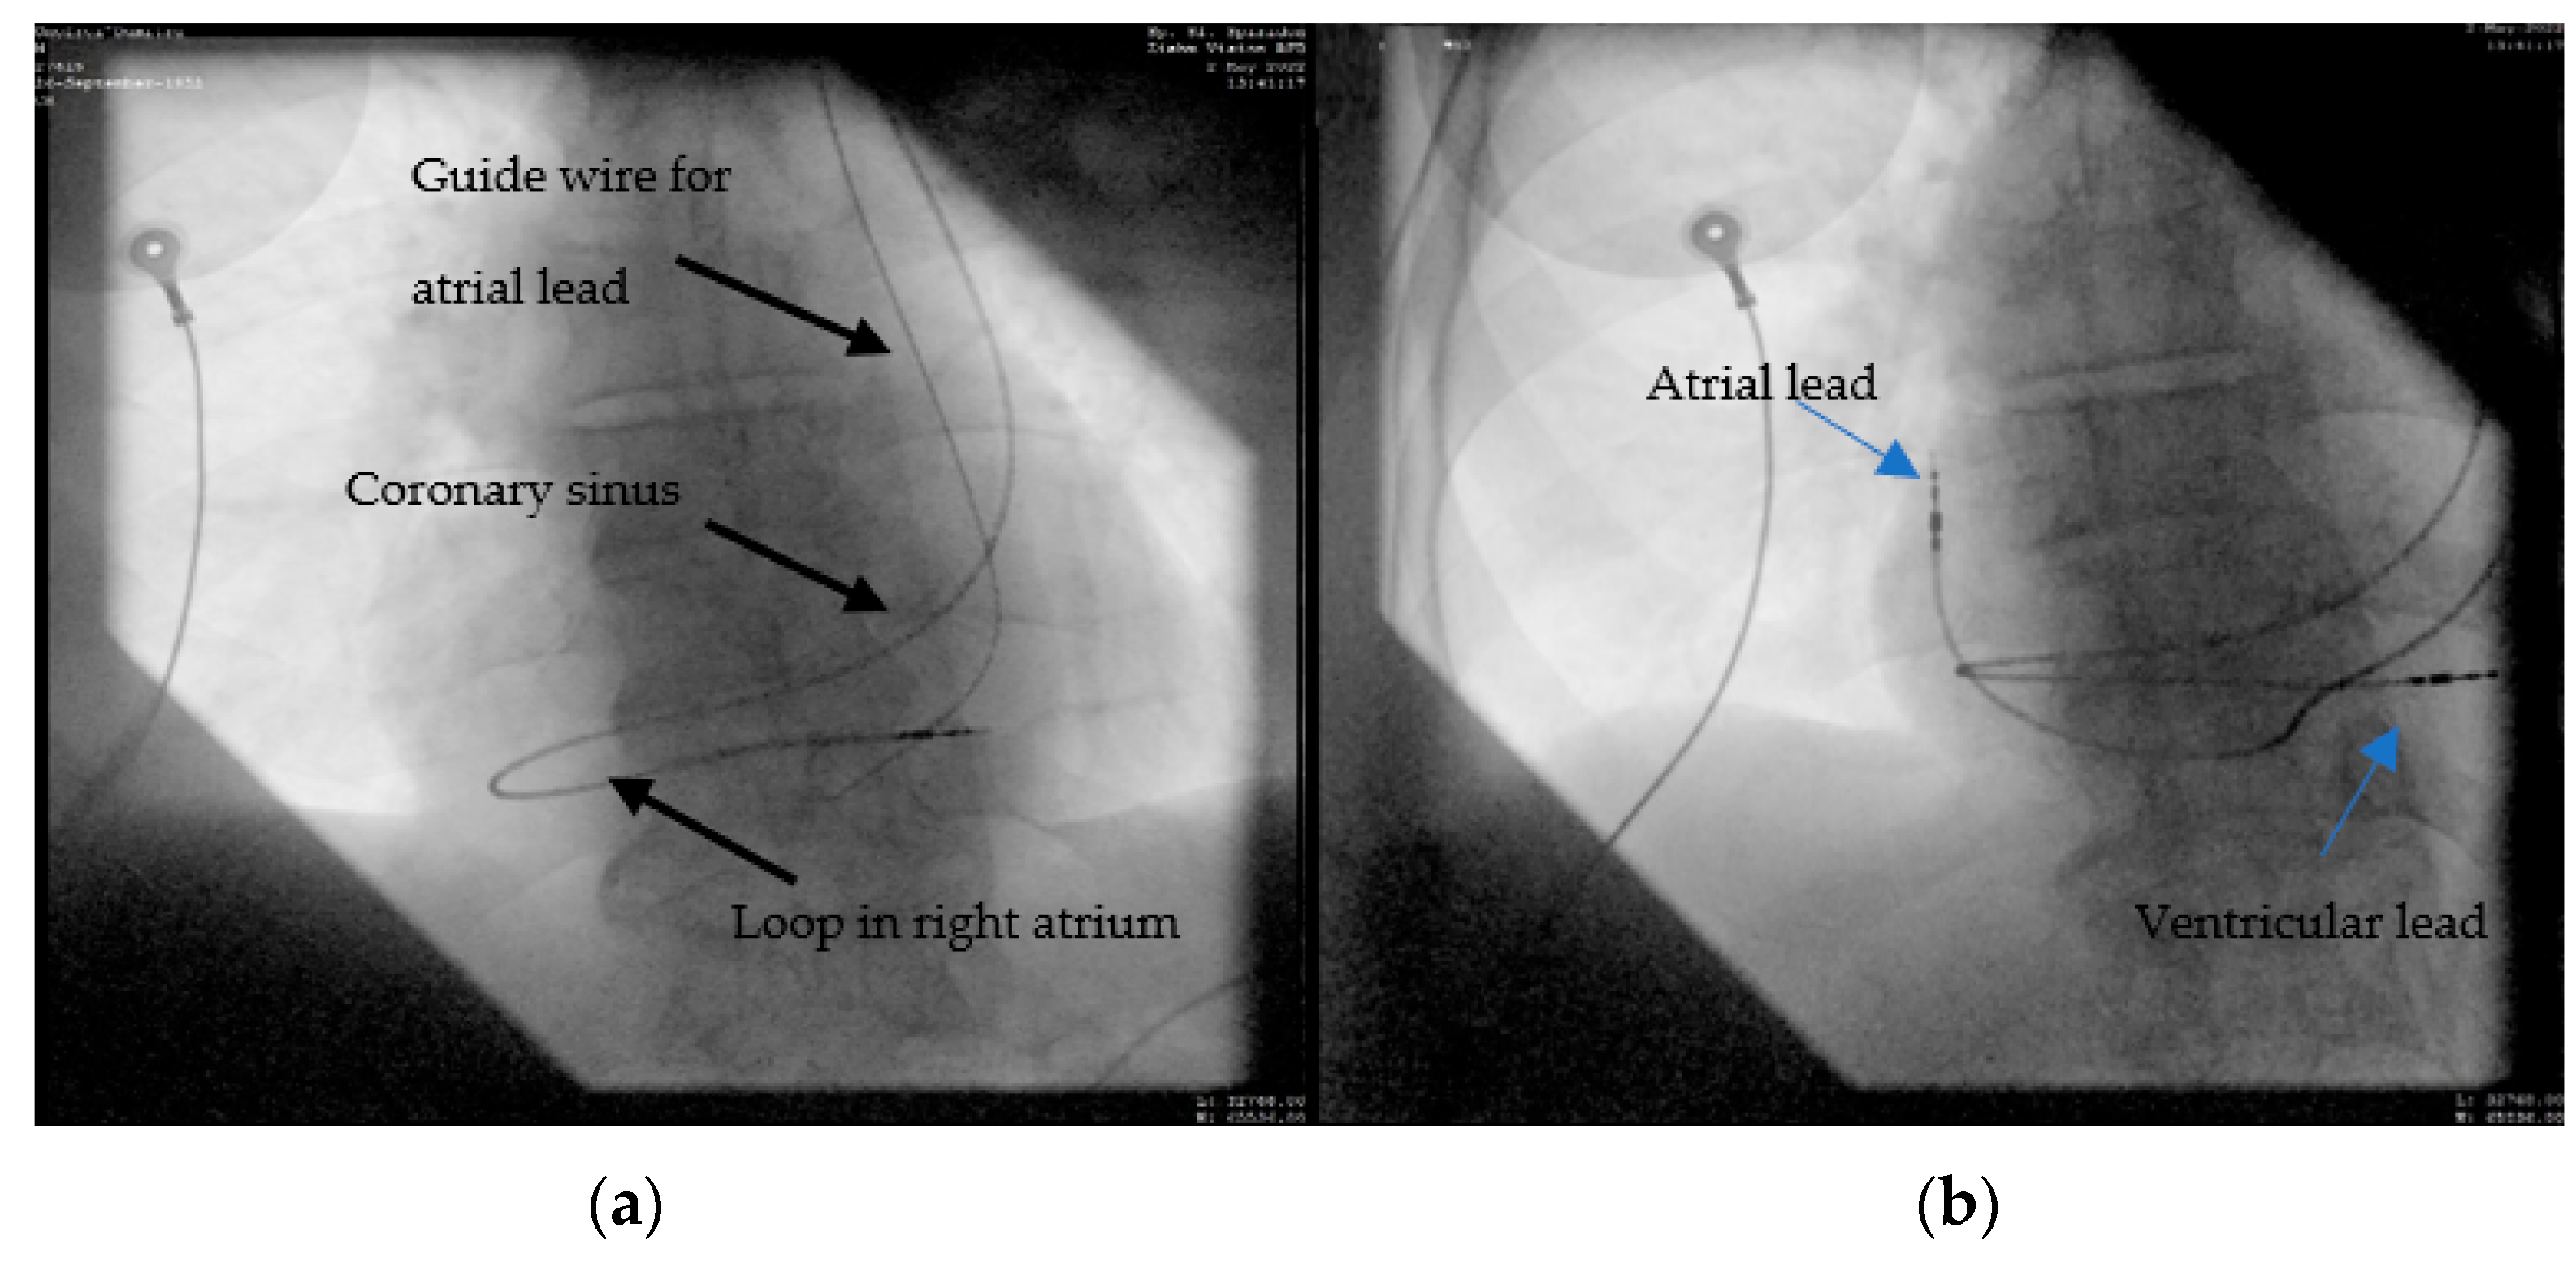

A 69-year-old male patient, diagnosed with sick sinus syndrome (tachycardia–bradycardia syndrome: sinus bradycardia alternating with paroxysmal atrial fibrillation (AF)), based on 24 h ECG Holter monitoring, symptomatic through syncope, was referred to our clinic for the implantation of a pacemaker. According to the current guidelines [8], the patient had an indication of a dual-chamber pacemaker. During this procedure, puncture of the left subclavian vein revealed as in other cases, an abnormal route of the guide wire. At that time, after a venography was performed, we knew that we are again dealing with another case of persistent left superior vena cava, but only post-procedurally; when thoracoabdominal angio-CT was performed, we had the confirmation that this was a case of type II PLSVC, which involves the embryological involution of right superior vena cava. Furthermore, during this exploration, it was found that this patient had multiple venous anatomical anomalies: right renal artery with two branches emerging from the aorta, left renal vein anterior, and posterior to the aorta (annular shape). The suspicion of its presence was raised pre-procedurally due to the increased size of the coronary sinus during the echocardiographic examination, but we did not have confirmation at that time. Just as in the first case, we adopted the same technique for the ventricular lead. Using a straight stylet, we passed through the coronary sinus, and then, with a J-shaped stylet, through the tricuspid valve in the right ventricle, leaving behind a significant loop of the lead at the level of the right atrium (Figure 5a). Finally, using the same route, the second lead was placed in the right atrial appendage (Figure 5b).

Figure 5.

Atrial and ventricular lead placement through PLSVC and coronary sinus: (a) the ventricular lead crossing a large coronary sinus and leaving behind a significant loop in the right atrium; (b) the final result with the leads at the level of the right atrium and right ventricular apex.

A 60-year-old female patient, with multiple cardiovascular risk factors (diabetes, dyslipidemia, hypertension), diagnosed with dilated cardiomyopathy with an ejection fraction of 15% and LV diameter of 64 mm 6 months ago, under maximal treatment for heart failure, was referred to our center after being diagnosed with sick sinus syndrome (tachycardia–bradycardia syndrome: sinus bradycardia alternating with paroxysmal atrial flutter) based on 24 h Holter ECG monitoring, symptomatic through syncope. A coronary angiography was performed, revealing normal epicardial coronary arteries, thus excluding an ischemic cause for the dilated cardiomyopathy. According to the current guidelines [9] in the primary prevention of sudden cardiac death, the next step was the implantation of a bicameral implantable cardioverter defibrillator (ICD). Left subclavian access was performed, but fluoroscopic evaluation again revealed an abnormal trajectory of the guide wire, raising the suspicion of a venous anomaly. Same as in case 2, the venography was performed through the subclavian vein, which evoked a persistent left superior vena cava, without any communication with the right superior vena cava (Figure 6a). Post-procedurally thoracoabdominal angio-CT revealed the presence of the right superior vena cava (type IIIb). This time, a 9F defibrillation lead (Medtronic Spring Quattro™, length 62 cm) was advanced through the coronary sinus in the right atrium, and again, using a J-shaped stylet, to the right ventricle, where it was placed at the apical level. In this case, we encountered some difficulties as we advanced the lead, which we passed by slightly retracting the stylet and leaving the tip of the probe free. After that, we placed the atrial lead at the right atrium level (Figure 6b).

Figure 6.

(a) The passage of the guide wire to the left side of the spine and then the venography confirming the presence of PLSVC, no communication with the right vena cava can be seen; (b) the defibrillation leads can be seen on the trajectory of the left superior vena cava (LSVC), through the coronary sinus (CS) into the right ventricular apex (RV)—red arrow. The atrial lead can be seen through the LSVC, coronary sinus, and right ventricle in the right atrial appendage (RA)—blue arrow.